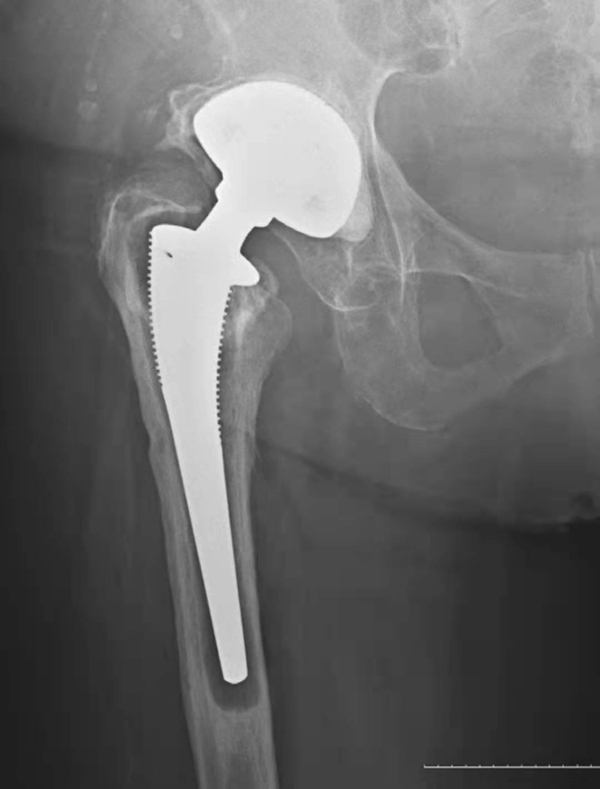

图3 无菌性松动

平片,示右侧髋臼杯周围骨质吸收,髋臼杯松动并向上内侧移位